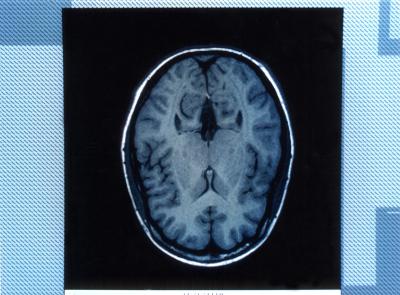

The study, which measured brain activity in test subjects who were trained to suppress memories of negative images, indicated two mechanisms in the prefrontal region of the brain were at work, said CU-Boulder doctoral candidate Brendan Depue, lead study author. The study may help clinicians develop new therapies for those unable to suppress emotionally distressing memories associated with disorders like post-traumatic stress disorder, phobias, depression, anxiety and obsessive-compulsive syndrome, he said.

The functional brain imaging scans taken during the study indicated the coordination for memory suppression occurred in the brain’s prefrontal cortex, considered by neuroscientists to be the “seat of cognitive control,” he said. The team found that two specific regions of the prefrontal cortex appear to work in tandem to suppress particular posterior brain regions like the visual cortex, the hippocampus and amygdala, which are involved in tasks like visual recall, memory encoding and retrieval, and emotional output, he said.

“These results indicate memory suppression does occur, and, at least in nonpsychiatric populations, is under the control of prefrontal regions,” the researchers wrote in Science. The most anterior portion of the prefrontal cortex highlighted in the study is a relatively recent feature in brain evolution and is greatly enlarged in humans when compared to great apes, said Depue.